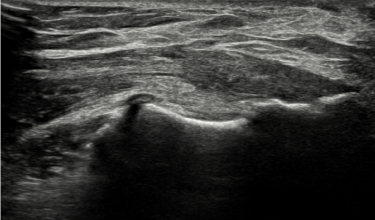

정상

테니스엘보